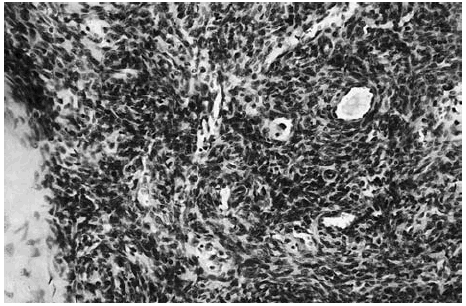

Se realizó una extirpación quirúrgica de la lesión. El estudio histopatológico mostró una tumoración dérmica multilobulillar con una zona central hipocelular, esclerosa y otra hipercelular en la periferia en la que se veían multiples espacios vasculares (fig. 2). Estas áreas más periféricas de espacios vasculares ramificados recordaban a un hemangipericitoma, y se continuaban insensiblemente con nódulos esclerosos. También se observaban nódulos hemangiopericitoides a distancia y sin conexión aparente con la tumoración principal (fig. 3).

Fig. 2.--Panorámica del tumor situado en dermis, con áreas esclerosas hipocelulares junto a otras hipercelulares. Destaca la presencia de hendiduras vasculares en la periferia de algunos nódulos.